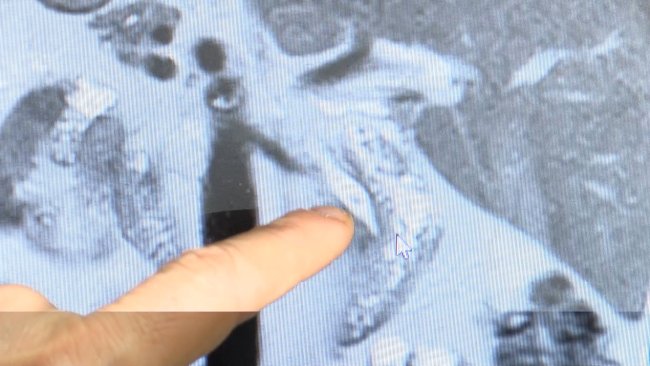

Yıllarca bu durumdan endişe duymayan Ak, geçen hafta karın ağrısı şikayetiyle Gazi Yaşargil Eğitim ve Araştırma Hastanesi'ne başvurdu. Burada röntgenleri çekilen Ak'ın safra kanalında taşlar olduğu tespit edildi.

Gastroenteroloji Uzmanı Dr. Mustafa Zanyar Akkuzu, "Hastamız karın ağrısıyla acil servise başvurmuştu. Hastaya yaptığımız tetkiklerde pankreas bezinde iltihap olduğunu gördük. Çektiğimiz röntgenlerinde bütün organların ters tarafında olduğunu gördük. Normalde bu anatominin dışında bir şeydir. Bütün organları ters taraftaydı. Bu tabii olguyu ilginç yapıyordu.

Pankreas iltihabının nedeni de safra kanalında ve kesesinde taş olmasıydı. Kanaldaki taşı almak böyle durumlarda zor oluyor. ERCP (Endoskopik retrograd kolanjiopankreatografi) işlemini rutin olarak hastanemize uzun yıllardır uyguluyoruz. Ancak hastanemizde organları ters olan bir hastada daha önce hiç uygulanmamıştı" dedi.

ERCP işlemine dair detaylardan bahseden Akkuzu, "Binde bir dahi olsa ölümcül riski olan bir işlem. Tabii anatomisi farklı olan hastalarda bu riskler daha fazla oluyor. Çünkü daha önce deneyimlemediğimiz bir işlem. Normal noktada açılmayan safra kanalı, tam tersi tarafında açılıyor. Böyle bir durumda tabii işlemi gerçekleştirmek, işlemin manevraları farklı bir şekilde düşünmek lazım. Normal ERCP işlemi başlı başına bir riskken, anatomisi farklı olan hastalarda daha büyük riskler oluyor.